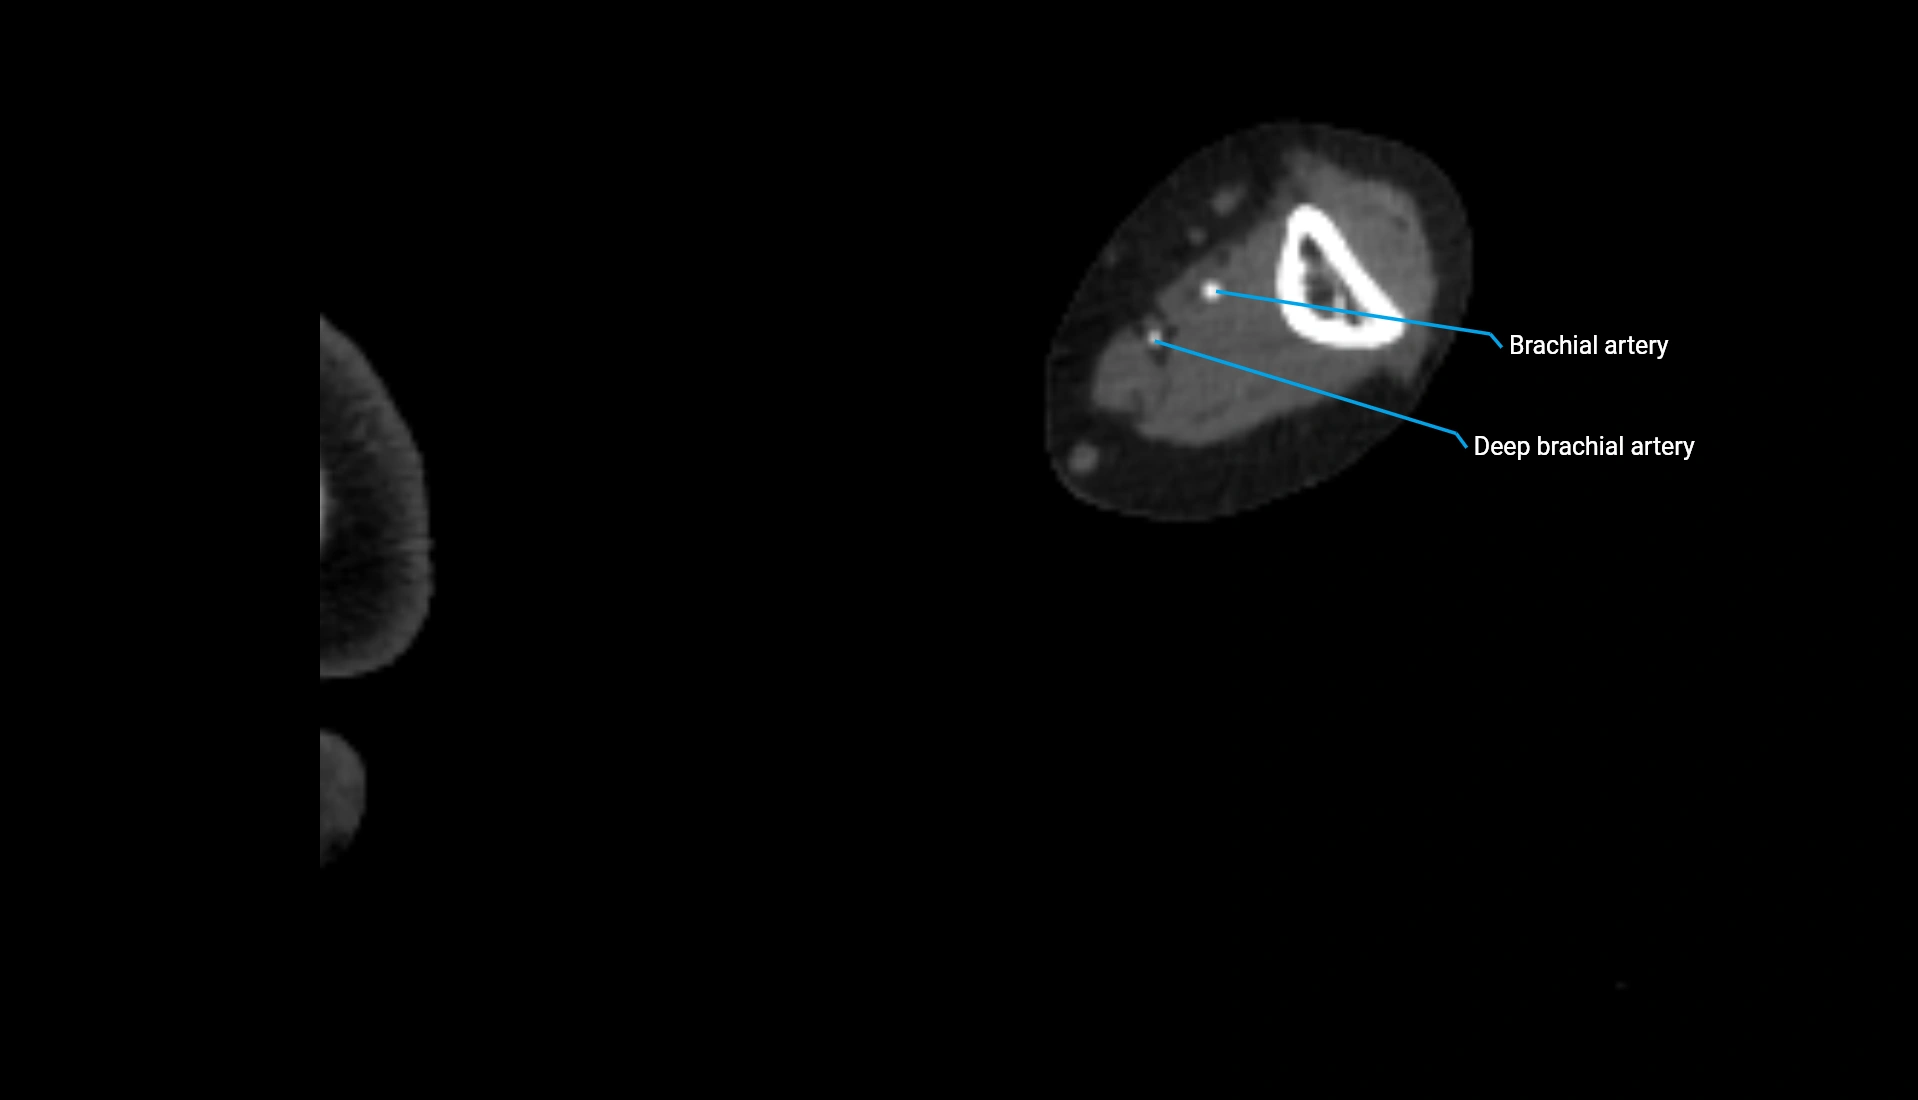

CT Appearance

Non-Contrast CT:

• Cortex: High-density, sharply defined

• Subchondral bone: Dense cancellous matrix

• Articular surface: Smooth concave contour articulating with the capitellum

• Excellent for evaluating bone integrity, alignment, and subtle fractures